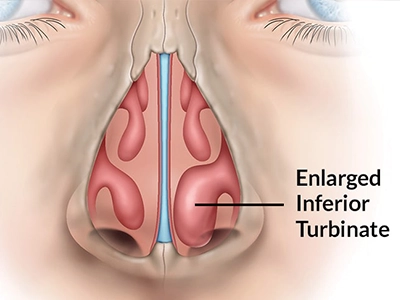

توجه ویژه به بهبود عملکرد تنفسی ( اصلاح انحراف تیغه بینی ، کاهش هیپرتروفی شاخکها در صورت نیاز).

در صورت نیاز، کاهش حجم شاخکهای بینی برای عبور بهتر هوا

جراحی زیبایی بینی (رینوپلاستی) تنها با هدف تغییر ظاهر انجام نمیشود؛ یکی از ارکان مهم موفقیت آن، حفظ یا بهبود عملکرد تنفسی است. پیش از عمل، ارزیابی دقیق مسیرهای تنفسی توسط جراح انجام میشود تا هرگونه انسداد، انحراف تیغه یا تنگی دریچههای بینی مشخص شود.

بررسی داخل بینی با آندوسکوپی برای مشاهده دقیق دریچهها و شاخکهای بینی

انجام تستهای عملکرد تنفسی (رینومانومتری) در صورت نیاز برای سنجش جریان هوای بینی

در موارد خاص، سیتیاسکن سینوس و بینی برای بررسی ساختار داخلی انجام میشود

ترکیب دقت در تحلیل زیبایی و ارزیابی عملکرد تنفسی باعث میشود نتیجه نهایی نهتنها از نظر ظاهری طبیعی و متناسب باشد، بلکه تنفس بیمار نیز بهبود یابد و از بروز عوارضی مانند گرفتگی یا تنگی مسیر هوا جلوگیری شود.